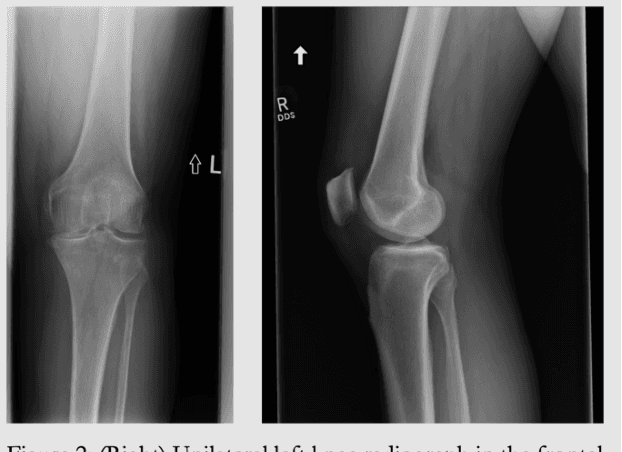

Abstract:The Emory Knee Radiograph (MRKR) dataset is a large, demographically diverse collection of 503,261 knee radiographs from 83,011 patients, 40% of which are African American. This dataset provides imaging data in DICOM format along with detailed clinical information, including patient-reported pain scores, diagnostic codes, and procedural codes, which are not commonly available in similar datasets. The MRKR dataset also features imaging metadata such as image laterality, view type, and presence of hardware, enhancing its value for research and model development. MRKR addresses significant gaps in existing datasets by offering a more representative sample for studying osteoarthritis and related outcomes, particularly among minority populations, thereby providing a valuable resource for clinicians and researchers.